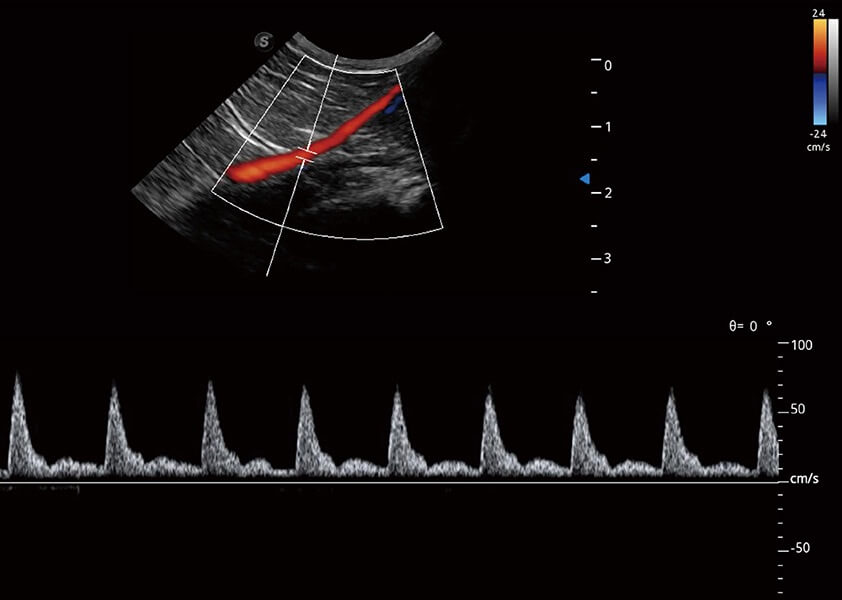

ProPet 60 作為一款高端臺(tái)式動(dòng)物超聲設(shè)備,為動(dòng)物醫(yī)生的日常診斷提供了一系列貼合動(dòng)物臨床需求、解決臨床實(shí)際問題的高級(jí)成像功能。憑借全系列高清探頭,滿足醫(yī)生對(duì)腹部、心臟、生殖、淺表、肌骨等成像的所有需求,切實(shí)幫助您提升檢查效率,提高診斷信心。